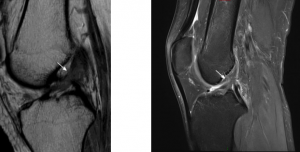

如图所示,前交叉韧带(ACL)部分撕裂的矢状位成像,前交叉韧带松弛张力消失,外观凹陷(白色箭头),信号强度增加。然而,纤维仍然是连续的,提示部分前交叉韧带撕裂。